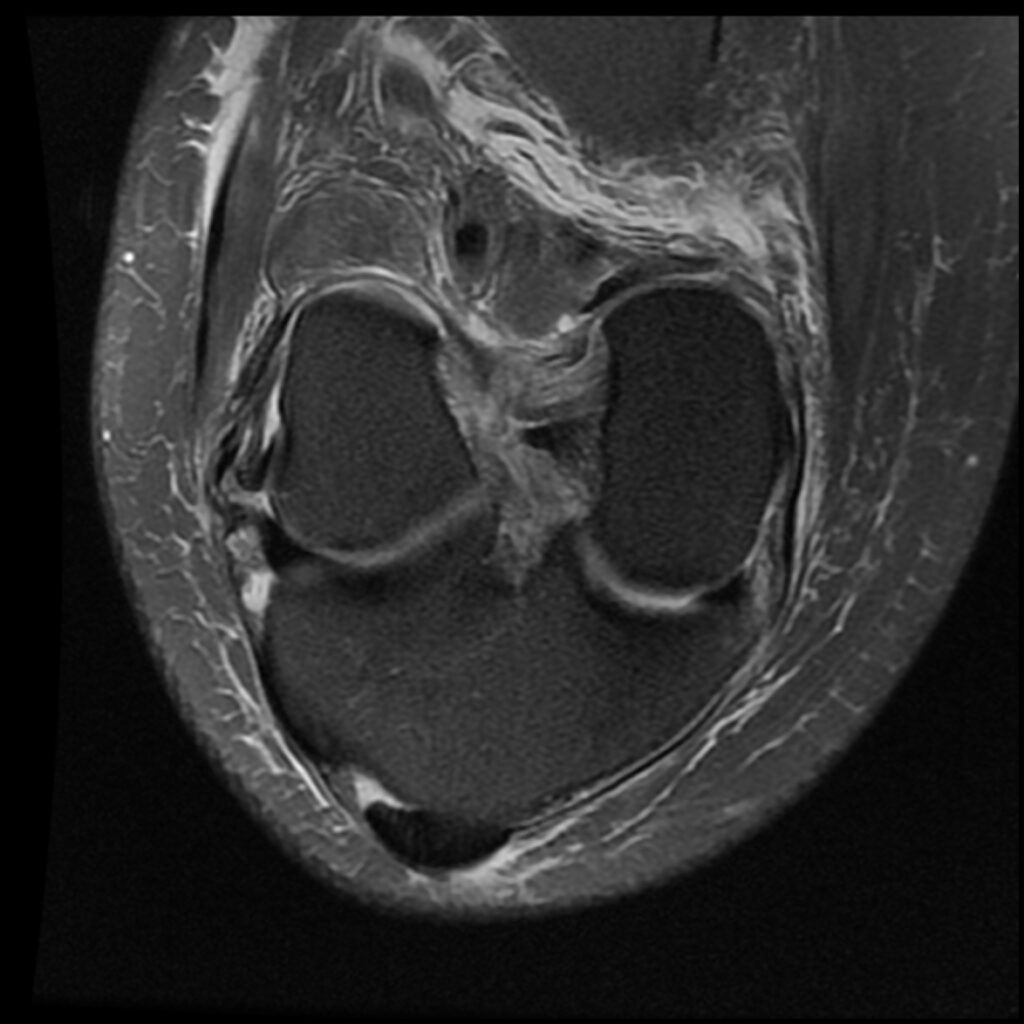

Patient C, age 44, was jumping on a trampoline when her foot got caught during rebound landing and forced the knee to extend and twist, tearing her ACL and medial meniscus and causing a Segond’s fracture, a posterolateral compression injury seen on the T2 sagittal MR images. Immediately upon becoming aware of her ACL injury, she asked my staff if she could put her “before & after” MR scans on my practice’s website after it healed. The initial treatment and aftercare were the same as patient D, aspirating any effusion and treating the posterolateral origin of the ACL. At 8-week follow-up, her knee was treated with hypertonic dextrose, with the collateral ligaments being treated with DGP. She was treated again at 16 weeks with another autologous PRP treatment of the knee joint, ligaments, and tendons. She was released to full sports and activities at 18 weeks post-injury. Subsequent MR scan revealed complete recovery of her ACL. Low grey signal replaced the original high signal intensity tear in the meniscus, appearing healed. Her knee was reported to be symptom-free at 5-year follow-up.

Patient C Before

Patient C After